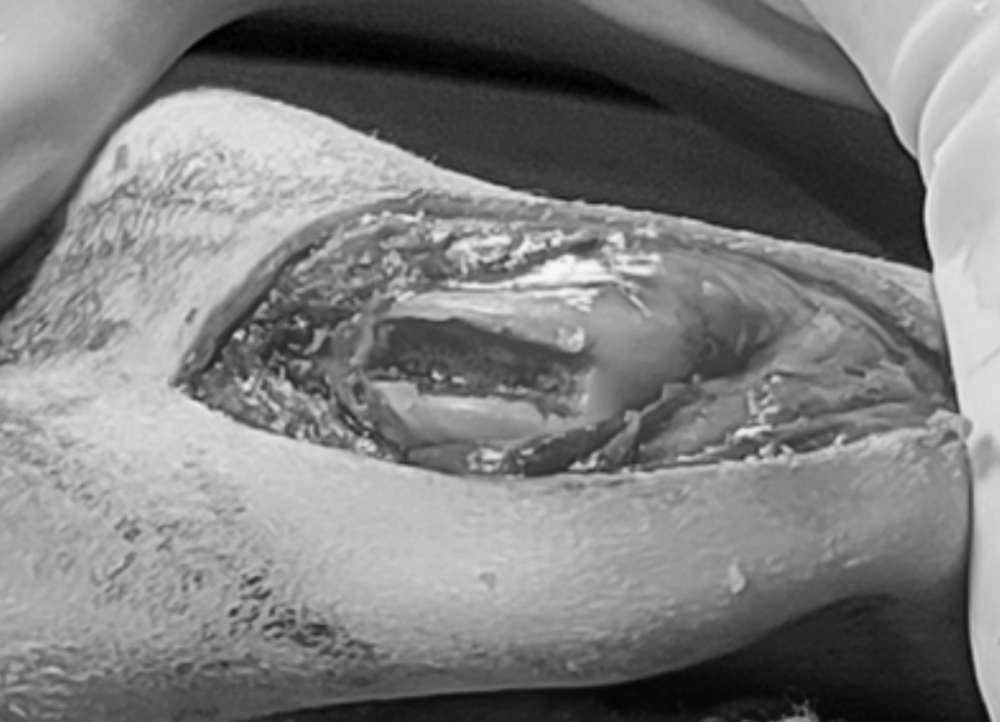

圖二:滑車溝加深

圖三:將膝蓋骨放回加深的滑車溝內